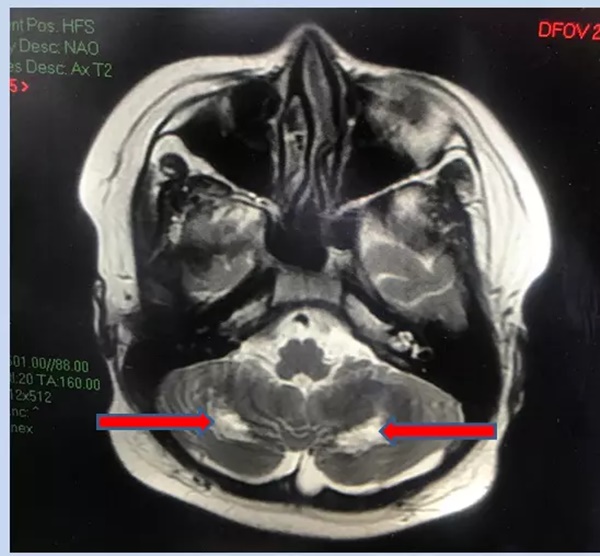

MRI cho thấy tổn thương chất trắng vùng tiểu não 2 bên gây hiện tượng rối loạn phối hợp vận động, loạng choạng ở bệnh nhi.

Xét nghiệm thấy phản ứng viêm trong máu tăng cao trở lại. Còn MRI não ghi nhận tổn thương đồi thị hai bên, tổn thương chất trắng của tiểu não. Bác sĩ chẩn đoán, bệnh nhi bị hội chứng viêm đa hệ thống, tổn thương não. H. được điều trị kháng viêm liều cao, kháng đông phòng ngừa tắc mạch.